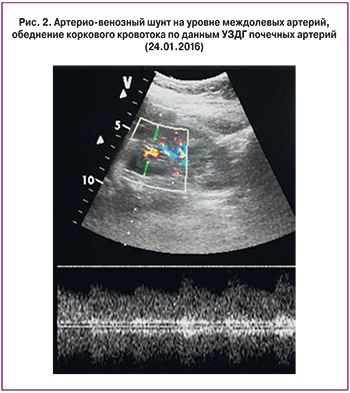

Учитывая тяжесть состояния больной и возможность дальнейшей генерализации ТМА с высоким риском развития угрожающих жизни осложнений, было принято решение о назначении экулизумаба. Перед началом терапии пациентка была вакцинирована противоменингококковой вакциной менцевакс. Первая инфузия экулизумаба в дозе 900 мг проведена на седьмые сутки пребывания в стационаре. В течение первой недели после введения препарата отмечено разрешение острого поражения почек: диурез быстро увеличивался и достиг 3200 мл/сут, СКр и мочевина в динамике снизились до 187 мкмоль/л и 12 ммоль/л, соответственно, скорость клубочковой фильтрации по клиренсу креатинина (проба Реберга) составила 23 мл/мин, что позволило прекратить процедуры гемодиализа. В общем анализе мочи – белок 1,6 г/л, эритроцитурия 30–40 в п/зр. При повторной УЗДГ почечных артерий отмечено появление коркового кровотока, хотя и сильно обедненного, с резким повышением индексов резистивности (RI) до 0,9. Отмечена быстрая положительная динамика гематологических показателей: к концу недели число тромбоцитов нормализовалось (263×109/л), уровень гемоглобина повысился, ЛДГ – снизился до 740 Ед/л, купирована гипергликемия. При повторной ЭГДС отмечено улучшение эндоскопической картины. Коагулограмма не имела значимых отклонений. Пациентка переведена на терапию низкомолекулярными гепаринами. В связи с необходимостью продолжения антибактериальной терапии в течение 2 недель после вакцинации произведена смена антибиотика – назначен тиенам в суточной дозе 1 г, продолжена в прежнем объеме симптоматическая терапия. После повторного введения 900 мг экулизумаба через семь дней после первого отмечена нормализация СКр (104–80 мкмоль/л), однако анемия сохранялась (гемоглобин 86 г/л). По данным повторной УЗДГ вен нижних конечностей отмечена начальная реканализация тромбоза глубоких вен. Выполненная в третий раз УЗДГ почечных артерий обнаружила улучшение показателей коркового кровотока: на фоне незначительного повышения RI (до 0,7) и снижения систолических скоростей отмечены единичные спектры с RI 0,48. Был выявлен также артерио-венозный шунт на уровне междолевых артерий (рис. 2). Такие допплерографические находки свидетельствовали о сохраняющейся ишемии почек как следствия тромботической блокады их микроциркуляторного русла. Об этом же свидетельствовала персистирующая протеинурия, которая колебалась от 0,8 до 1,5 г/сутки и практически исчезла только через 3 месяца после начала терапии.

Наличие ренальной ТМА как основного проявления аГУС мы подтвердили с помощью УЗДГ почечных сосудов, которая может служить основным неинвазивным методом диагностики окклюзивного поражения микроциркуляторного сосудистого русла почек, независимо от механизма его развития [15, 16]. Выявленные у пациентки обеднение дистального почечного кровотока в режиме цветного допплеровского картирования, снижение скоростных показателей в дуговых и междолевых артериях в сочетании с мозаичностью кровотока на уровне этих сосудов отражают ишемический характер внутрипочечного процесса. Выраженность изменений зависит от остроты процесса, что подтверждают результаты исследований, выполненных нашей больной в динамике. Кроме того, по данным ряда исследователей, УЗДГ позволяет дифференцировать почечную ТМА от острого канальцевого некроза вследствие, например, массивной кровопотери [17]. Таким образом, выявленные ультразвуковые признаки высоко специфичны для ТМА независимо от ее генеза, что позволяет считать УЗДГ ценным диагностическим методом, дополняющим и в ряде случаев заменяющим морфологическое исследование ткани почки при ТМА.